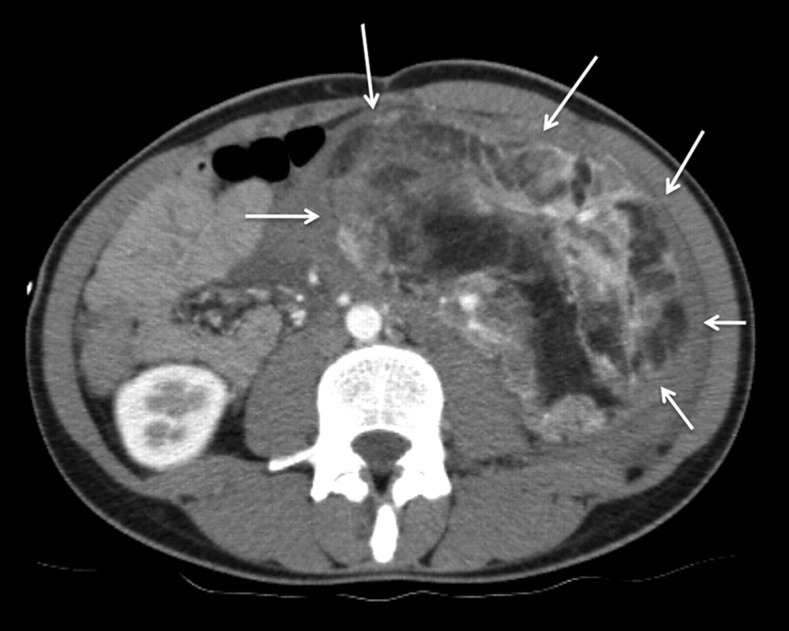

我们报告一位36岁的白人妇女,她以计算机断层扫描诊断为创伤后腹膜后出血而来到急诊室。患者临床稳定后,进行选择性动脉栓塞。血管平滑肌脂肪瘤的供血动脉用8毫米Amplatzer II型血管塞成功治疗。左肾上极由独立的肾上动脉供应,保存完好。结果,肾血管平滑肌脂肪瘤坏死,手术切除整个肾血管平滑肌脂肪瘤。本病例说明了一种简单有效的应用Amplatzer血管堵塞器进行血管栓塞,而无需额外缠绕。

We report on a 36-year-old Caucasian woman who presented to the emergency department with post-traumatic retroperitoneal bleeding diagnosed by computed tomography. After clinical stabilization of the patient, selective arterial embolization was performed. The angiomyolipoma's feeding artery was successfully treated with an 8-mm Amplatzer Vascular Plug Type II. The upper pole of the left kidney, which was supplied by a separate upper renal artery, was conserved. Consequently, the renal angiomyolipoma became necrotic and surgical resection of the entire renal angiomyolipoma was performed. This case illustrates a simple and effective application of an Amplatzer Vascular Plug occluder for vessel embolization, without additional coiling.